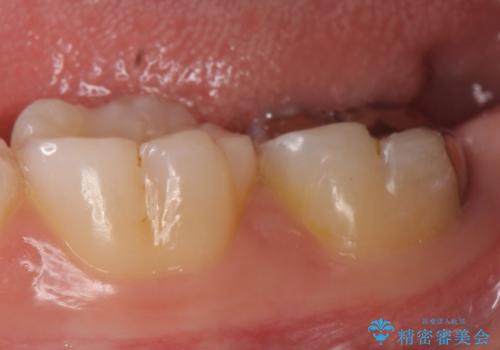

その後歯茎の治りを待ちポケットが正常値であることを確認後、オールセラミッククラウンによる補綴を行いました。

今回用いたオールセラミッククラウンはジルコニアフレームという白い素材の上にセラミックを盛っているため、審美性が非常に高いのが特徴です。

また、ジルコニアは人工ダイヤモンドの材料にも使われているほど高い強度を持っており、そのためオールセラミッククラウンは審美性だけでなく、奥歯やブリッジの補綴も可能とするクラウンです。